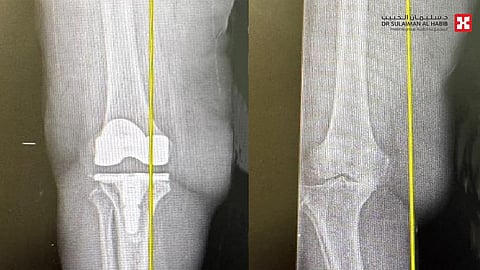

وأضاف أن المراجعة خضعت لفحوصات دقيقة، حيث كشفت صور الأشعة السينية عن وجود خشونة حادة في مفصل الركبة، وتلف بالأربطة، فقام الفريق الطبي بوضع خطة علاجية متكاملة، بعلاج هشاشة العظام، بعدها أخضعت لعملية متقدمة باستخدام تقنية الروبوت الجراحي، وتحت التخدير النصفي، وتم فيها تعديل التقوس الحاد باستخدام دعامة لتعويض تصلب وضعف الأربطة، ومن ثم استبدال مفصل الركبة بآخر صناعي عالي الجودة ومناسب للحالة. استغرقت العملية نحو "90" دقيقة، وتكللت ولله الحمد بالنجاح التام، وتمكنت المراجعة من المشي بعد ساعات قليلة من العملية، وغادرت المستشفى بعد عدة أيام، وهي بحالة صحية جيدة، ولاحقاً تخلصت من كافة الأعراض التي عانت منها طوال عامين، وعادت لممارسة حياتها الطبيعية.